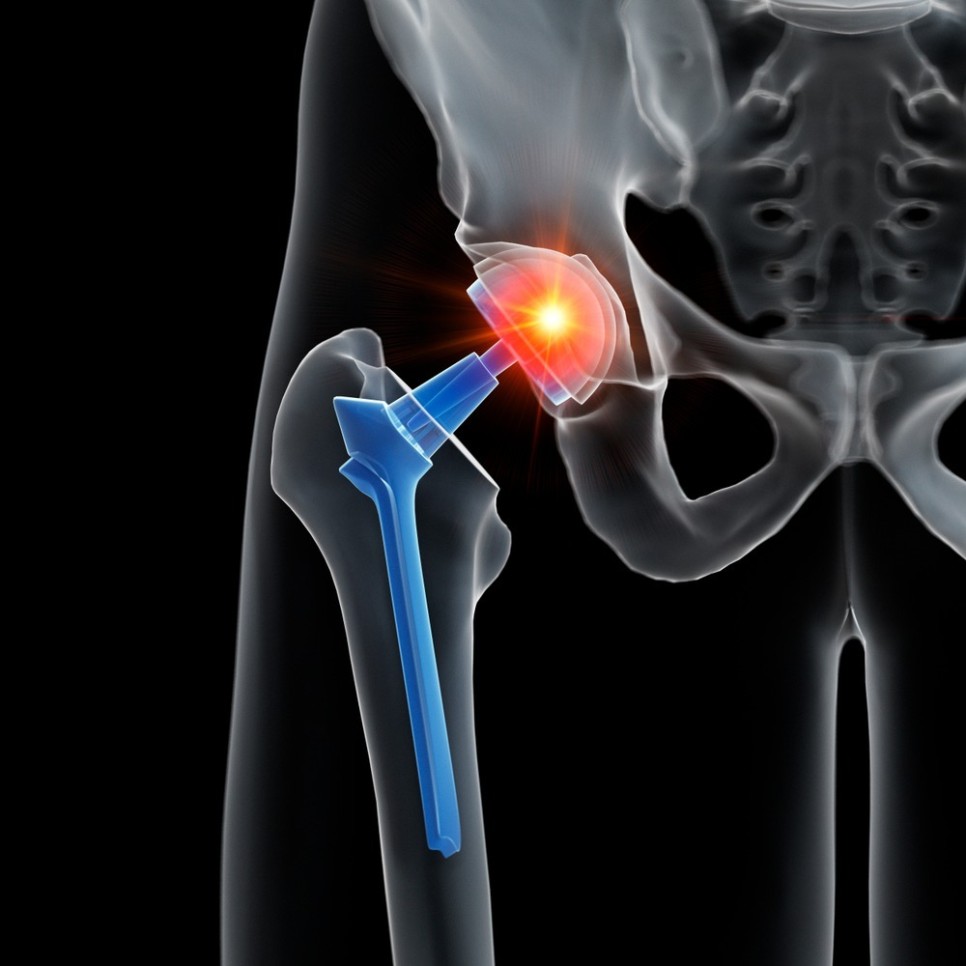

'대퇴골두 무혈성 괴사' 수술 방식은?

대체로의 대퇴골두 무혈성 괴사는

인공고관절치환술을 시행합니다.

이 수술법은 대퇴골두의 괴사된 골두를

제거하고, 그 부위에 특수 금속과 플라스틱

재질로 인공고관절을 삽입하는 수술인데요.

인공관절은 환자 개개인의 관절에 가장

적합하게 디자인된 인공관절을 사용하며,

컴퓨터를 통한 첨단 네비게이션을 시스템을

이용하므로 오차 없이 정확한 위치에 최적의

각도로 인공관절을 삽입합니다.